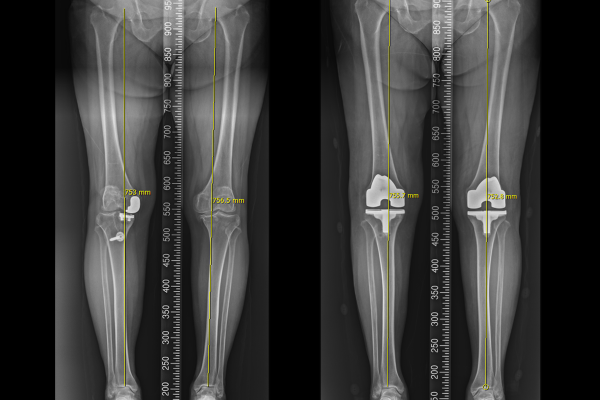

기존 인공관절을 잘 제거하고서, 3D 기술을 통해 환자분에게 맞춤형으로 제작된 인공관절로 교체해드렸습니다. 전치환술 후 X-RAY를 보면 잘 치환된 것이 확인됩니다.

3D 기술을 이용한 환자 맞춤형 인공관절 전치환술에 대한 내용은 전에 작성하였던 블로그 글을 첨부하오니, 궁금하신 분들께서는 참고해주시길 바랍니다.

수술 후 다리 정렬을 보면 일자로 곧게 체중축이 교정된 것이 확인됩니다.(좌측 무릎도 안좋으셨기 때문에, 우측 재수술 후 약 일주일 뒤에 좌측 무릎 인공관절 전치환술도 시행하였습니다.)